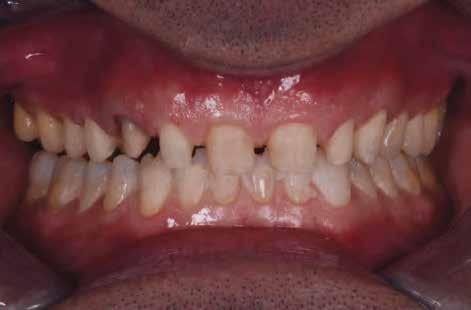

„Andrea" esete lenyűgöző példa arra, hogy egy fogászati team hogyan adhat új életet valakinek. Digitális ideiglenes fogsor készítésével a fiatal páciensnél komoly életminőség-javulást értek el.

A cikkben egy fiatal nő kezelésének interdiszciplináris megközelítését foglaltuk össze, aki fogászati állapota miatt hoszszú ideje szenvedett fizikálisan és pszichésen is (1. ábra)

Az ilyen esetek megoldásához elengedhetetlenek - a fogászati és fogtechnikai know-how mellett - a jól bevált kommunikációs gyakorlat a praxis és a laboratórium között, valamint a gyártási technológiák összehangolása. A végeredményhez az ideiglenes megoldáson keresztül vezetett az út, mely „normális” funkcionális és esztétikai helyzetet tett lehetővé.

Amikor a 25 éves Andrea először konzultált a rendelővel, már több éve küszködött súlyos panaszokkal. Állapota két különböző betegségnek köszönhető, melyek egyrészt önmagukban, másrészt egymással kölcsönhatásban is súlyos következményekkel jártak. A fiatal nő veleszületett genetikai elváltozásban szenved, melynek tünete többek között a gyenge zománcfejlődés. Továbbá a beteget fibromyalgiával is diagnosztizálták, mely krónikus fájdalom rendellenesség, ami komoly tünetegyüttessel járó pszichés szorongás. A betegség egyik következménye az volt, hogy a páciens az elmúlt években átlagosan napi három-négyszer hányt. Az ebből fakadó savas erózió a már amúgy is veszélyben lévő fogazatot tovább roncsolta (2. ábra)

A betegség következményei

A páciens elviselhetetlen fájdalmakról számolt be, beleértve a többszörös szájüregi fertőzéseket is. Az elmúlt években az előírt számos antibiotikumos kezelés egyre gyengébb hatásfokkal működött. A fertőzések következtében több fogát is extrahálni kellett. A fogászati állapotával együtt az étkezés minősége is romlott. A súlyos esztétikai korlátok is terhet jelentettek. A psziché és az önbizalom komoly károkat szenvedett. Fogorvosnál tett korábbi látogatásai kellemetlen élményt jelentettek. Emiatt kezdetben vonakodott beleegyezni a komplex terápiába. Empatikus, érzékeny beszélgetések folyamán körvonalazódott számára a kezelés fontossága.

A fogak extrahálása és az alveoláris plasztika teljes narkózis mellett történt meg, így teremtve ideális helyzetet a protetikai ellátáshoz. A műtéti beavatkozás után a páciens az ideglenes fogsorral távozott. Egy héttel később jött kontrollra. Nemcsak látványra változott meg nagymértékben, hanem egyértelműen magabiztosabb és önbizalommal teli volt a fellépése (12. ábra)

Az elsődleges terápiás szakasz kulcsfontosságú volt a teljes rehabilitáció szempontjából. A páciensnek nem csak szép, esztétikus mosolyt kölcsönzött, hanem életminőségének javulását is hozta (13. ábra). A Digital Denture folyamatnak köszönhetően a kezelés ráfordításai is alacsonyak voltak. A fiatal nő messzemenően boldog, magabiztos és motivált a következő lépéshez.